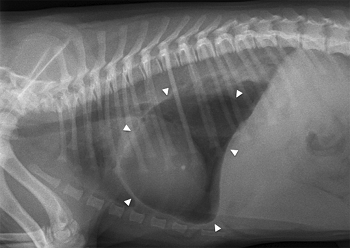

In a

November 2019 article, UK and Swiss researchers reported on five separate cases of

cavalier King Charles spaniels diagnosed with a congential defect in the

diaphram causing the stomach and/or other abdominal organs to herniate

into the chest cavity. All of the affected cavaliers were intact males,

four of the

between 2.5 months and 9 months old, and the fifth dog was 18 months

old. The cases occurred over a period of 12 years. The symptoms were

rapid breathing and shortness of breath. In all of the dogs, chest

x-rays showed a gas-fluid-filled structure on the left side of the

chest, which was found to be the stomach (see photo at right), with some degree of lung collapse and shift to the opposite side.

The clinicians determined that the dogs developed "tension

gastrothorax", which describes the stomach herniating through a

congenital diaphragmatic defect into the thorax and distended due to

being filled with trapped air. One of the CKCSs was euthanized, and

surgery was performed on the other four. The stomach was herniated into

the chest cavity in all five cases, and in others, the spleen and/or

omentum and/or intestine also was herniated. The hernias were repaired

and all four of the surviving dogs recovered successfully. The authors

concluded:

"In this report, all cases were purebred CKCS; they were presented in a timespan of approximately 12 years, and no information was available regarding their pedigree. Genetically inherited disease in CKCS includes mitral valve disease, syringomyelia, congenital and juvenile cataract and multi-focal retinal dysplasia. Based on this report, CKCS could also be a breed predisposed to pleuroperitoneal diaphragmatic hernia, but extensive breeding studies would be necessary to evaluate this hypothesis. Interestingly, all the cases were male, suggesting the possibility of a sex chromosomal mode of inheritance."